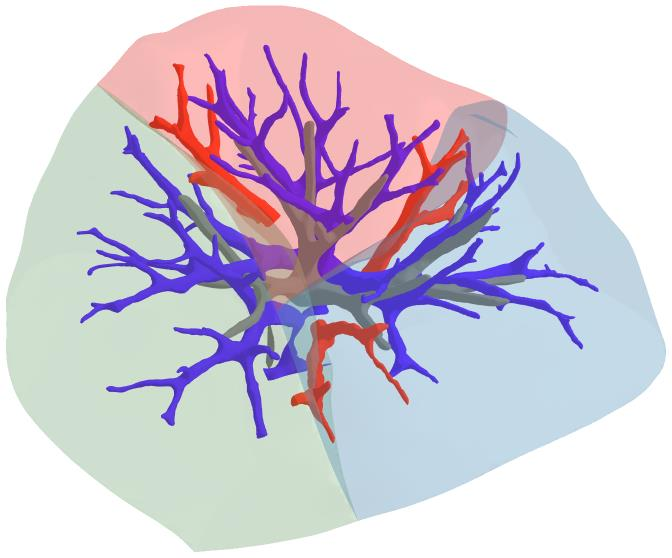

3D reconstruction of pulmonary segments plays an important role in surgical treatment planning of lung cancer, which facilitates preservation of pulmonary function and helps ensure low recurrence rates. However, automatic reconstruction of pulmonary segments remains unexplored in the era of deep learning. In this paper, we investigate what makes for automatic reconstruction of pulmonary segments. First and foremost, we formulate, clinically and geometrically, the anatomical definitions of pulmonary segments, and propose evaluation metrics adhering to these definitions. Second, we propose ImPulSe (Implicit Pulmonary Segment), a deep implicit surface model designed for pulmonary segment reconstruction. The automatic reconstruction of pulmonary segments by ImPulSe is accurate in metrics and visually appealing. Compared with canonical segmentation methods, ImPulSe outputs continuous predictions of arbitrary resolutions with higher training efficiency and fewer parameters. Lastly, we experiment with different network inputs to analyze what matters in the task of pulmonary segment reconstruction. Our code is available at https://github.com/M3DV/ImPulSe.